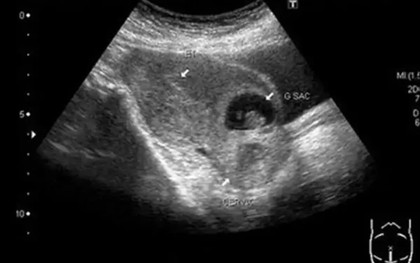

Băng huyết nguy kịch sau khi tự phá thai tại nhà

Bệnh viện Sản Nhi Quảng Ninh vừa báo động đỏ toàn viện, huy động nhân lực tham gia hiến máu, cấp cứu thành công bệnh nhân bị băng huyết sau khi tự ý phá thai tại nhà.